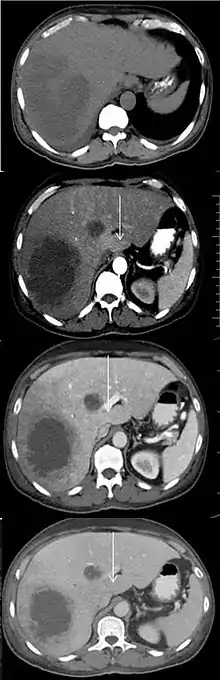

An abscess and a THAD (white arrow) on a contrast CT in native, arterial, portal and delayed phase.[1]

Transient hepatic attenuation differences (THAD) are areas of enhancement during the arterial phase of contrast CT of the liver. THAD is thought to be a physiological phenomenon resulting from regional variation in the blood supply by the portal vein and/or the hepatic artery. THAD may in some cases be associated with liver tumors such as a hepatocellular carcinoma.[2]